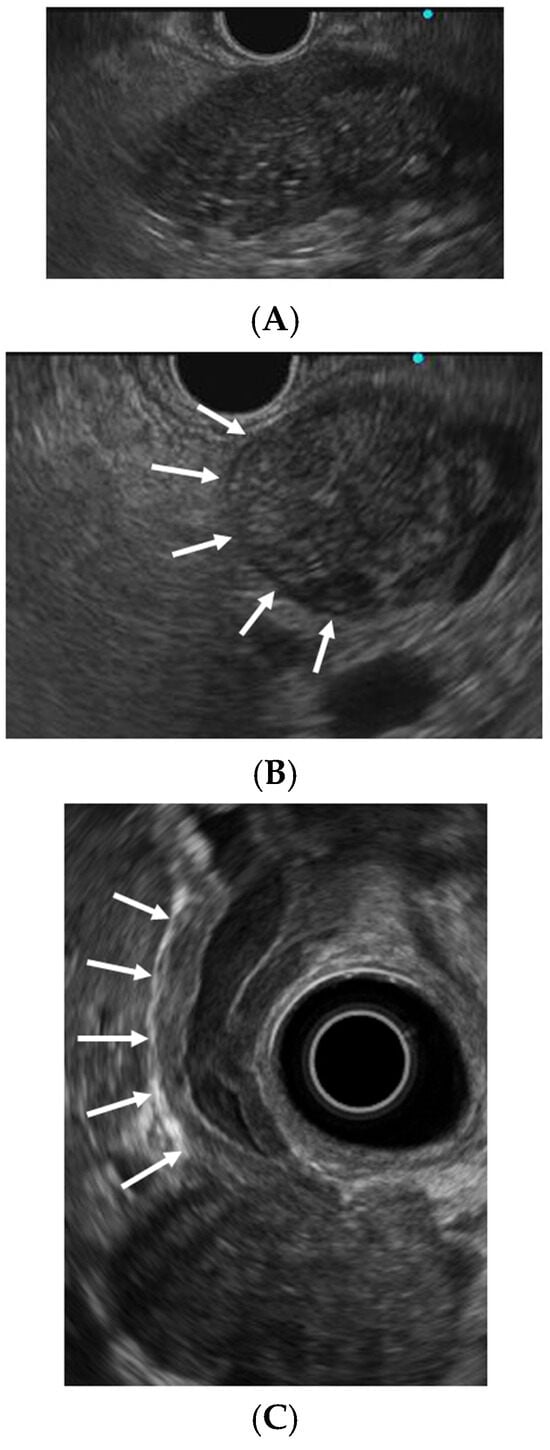

EUS is used to assess pancreatic enlargement in the diagnosis of AIP. Characteristic conventional EUS findings include diffuse pancreatic enlargement with a hypoechoic (“sausage-like”) appearance, peripancreatic hypoechoic margins, and bile duct wall thickening (Figure 1) [8,13,23,24]. Focal pancreatic enlargement must be distinguished from PC. A notable differentiating feature is the duct-penetrating sign, defined as an uninterrupted MPD traversing the mass without obstruction (16). In a retrospective study of 285 patients with AIP, Zhan et al. [25] reported hypoechoic areas (74.7%), bile duct wall thickening (68.4%) or stenosis (57.9%), peripancreatic lymphadenopathy (31.2%), and peripancreatic hypoechoic margins (28.4%) as common findings on conventional EUS.

Figure 1.

Endoscopic ultrasonographic findings of autoimmune pancreatitis and IgG4-related sclerosing cholangitis. (A) Diffuse pancreatic enlargement with a hypoechoic (“sausage-like”) appearance. (B) Peripancreatic hypoechoic margin (arrows). (C) Bile duct wall thickening (arrows).